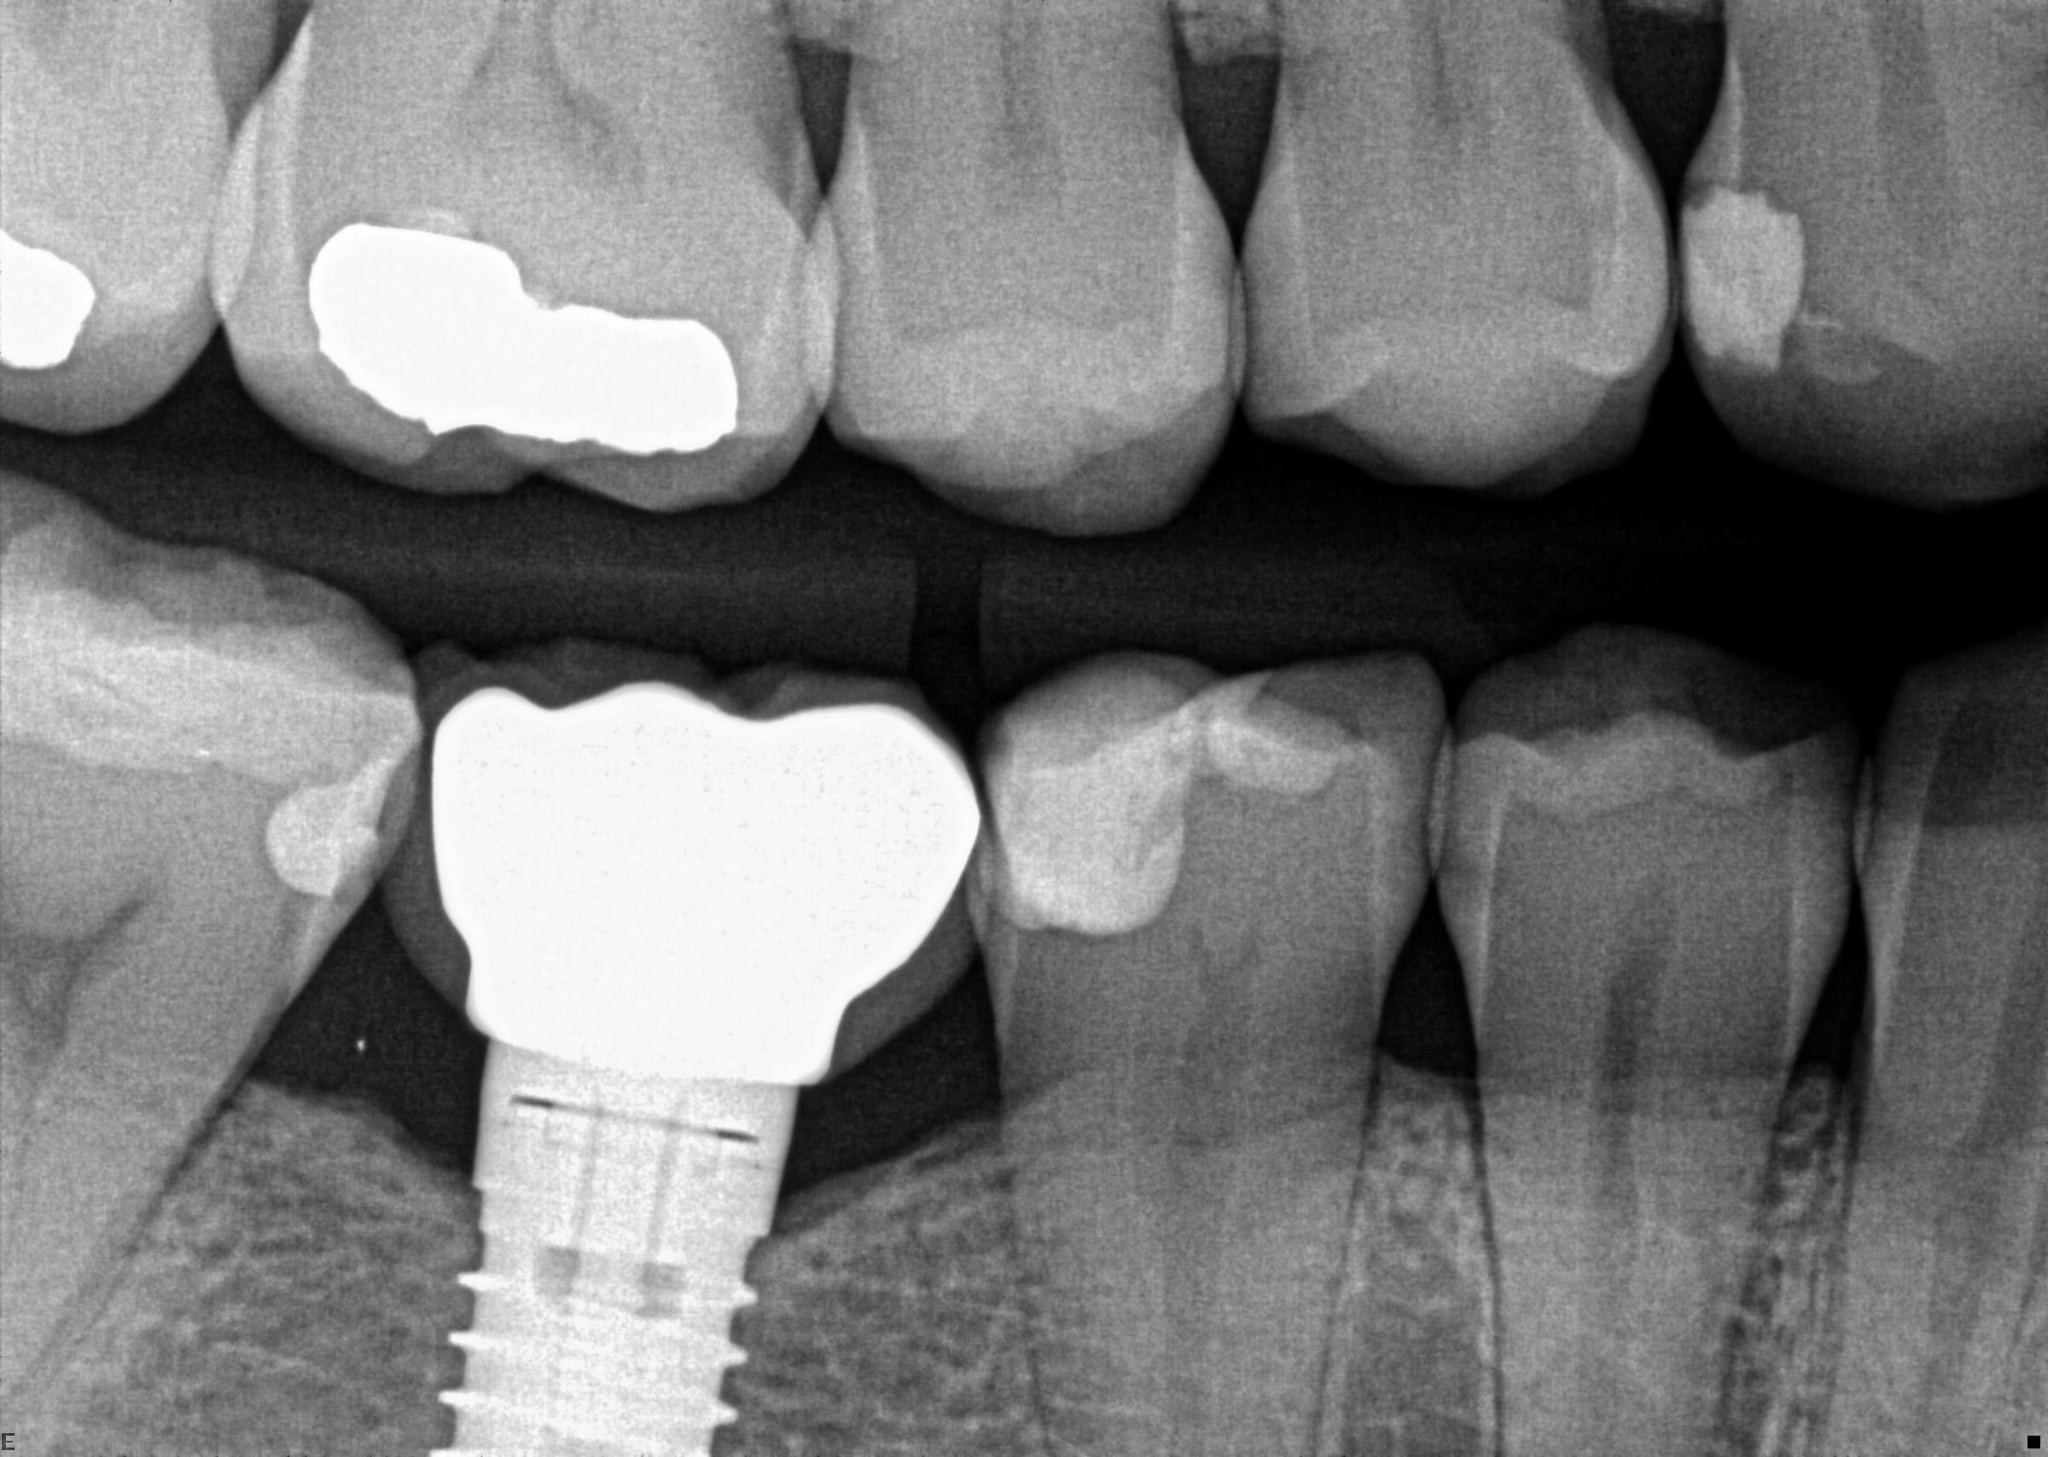

18 / 35

18. On which surface a recurrent caries can be detected?

crowns mostly show open margin not recurrent caries

19 / 35

19. On which surface a recurrent caries can be detected?

This is the PA X ray of the question # 18, based on this X ray recurrent X ray for distal tooth # 3.7 can also be selected